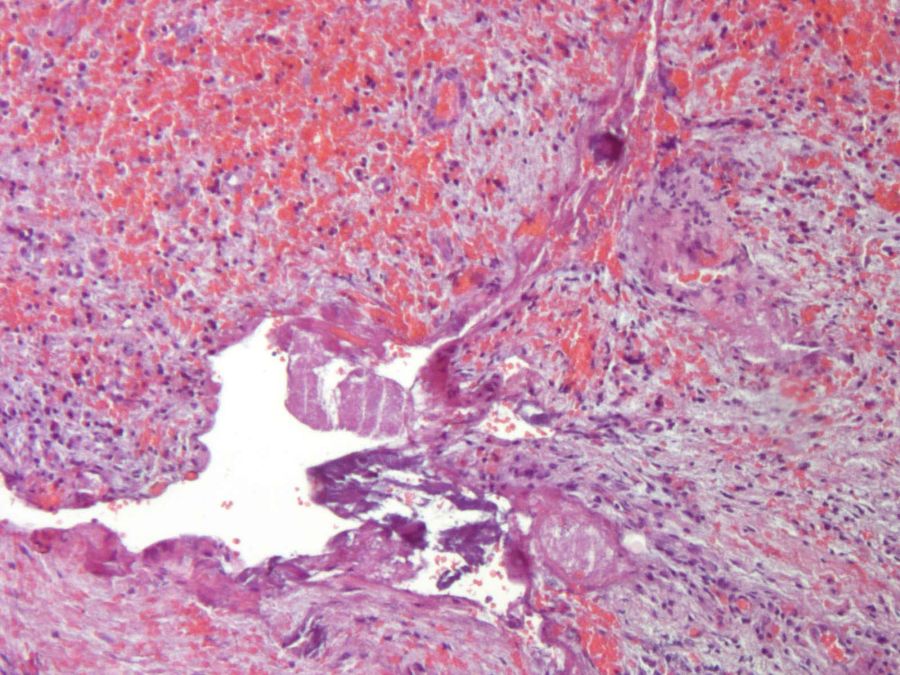

La muestra obtenida fue enviada en formaldehído al 10% para su análisis histopatológico, informando de los siguientes hallazgos:

- Descripción macroscópica: se remiten dos fragmentos, membranáceos, irregulares, parduzcos con zonas negruzcas, que miden en conjunto 1×1,2×0,5cm. se secciona el mayor y se incluyen en su totalidad.

- Descripción microscópica evidencia una lesión quística con una pared conectiva fibrocelular gruesa definida con estructuras vasculares dispersas y focos de inflamación crónica linfoplasmocitaria, hemorragia y depósitos hemosiderina. También se observan focos de inflamación mixta con numerosos macrófagos espumosos. En uno de los fragmentos se reconoce un recubrimiento epitelial poliestratificado no queratinizado fino delgado, focalmente desprendido. Periféricamente se observa una cáscara de tejido óseo vital trabecular (Figuras 13 y 14). El diagnóstico definitivo fue de quiste dentígero con inflamación crónica.